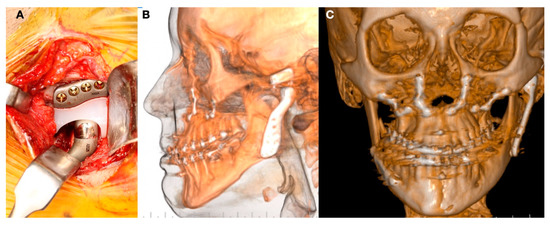

1.3. Clinical Conditions Related to Use of TMJ Replacement

- Volume and Size Augmentation of the Mandibular Condyle

- Volume and Size Reduction of the Mandibular Condyle

- Malformations, Pathology, or Trauma of the Mandibular Condyle